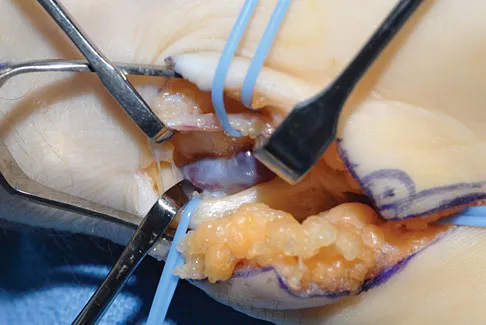

A 16-year-old boy with osteochondritis dissecans of the capitellum has intermittent symptoms of catching and locking. Examination is unremarkable. Radiographs reveal a loose body anteriorly with a diameter of 10 mm. To remove the loose body, elbow arthroscopy is being considered. Which of the following procedures would minimize the risk of neurovascular complication during the procedure?

A 21-year-old professional baseball player has had painful catching and stiffness in his dominant right elbow for the past year. Examination reveals a flexion contracture of 2 degrees and mild pain with full elbow flexion. Radiographs are shown in Figures 33a and 33b. The most effective management should consist of